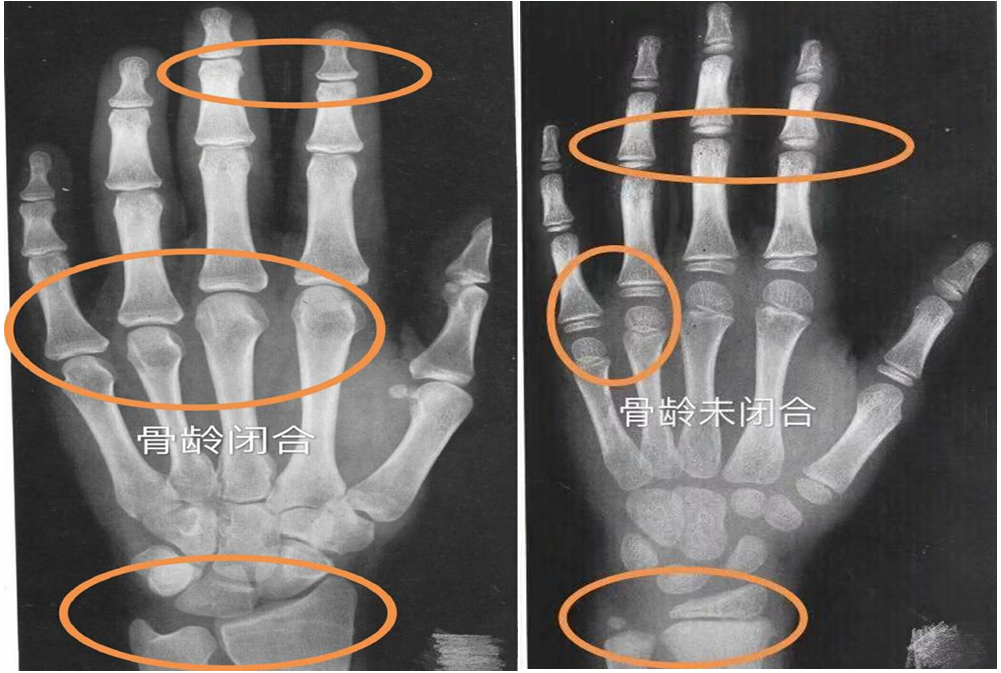

矮小、性早熟门诊主任刘静介绍,人的身高增长是有时限的,临床医学表明,一般情况下,人的骨骺在14-15岁就会闭合,一旦骨骺闭合,任何方法都不可能再长高。因此,家长需要尽早关注孩子身高,早发现身高落后或过早发育,尽早来就诊评估。说到评估身高,不得不提骨龄。人的生长发育可用两个“年龄”来表示,即生活年龄(日历年龄,CA)和生物年龄(骨龄,BA)。临床上通过拍摄左手腕部的X光片,观察指骨,腕骨及桡、尺骨下端的骨化中心出现的时间、大小、形态等,诊断骨骼实际发育程度,来确定骨龄。骨龄能较准确地反映生长发育水平和成熟程度,了解儿童的生长潜能以及性成熟的趋势,是预测儿童的成年身高的重要依据。